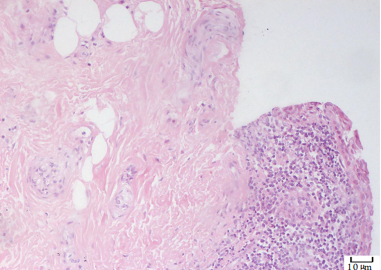

20230608171256_8542.png

图2 (眼角)皮肤组织及结膜组织显示重度慢性炎症,部分区伴急性炎症,乳头状瘤样增生,过度角化及不全角化(HE,×200)

Figure 2 The skin tissue and conjunctival tissue showed severe chronic inflammation, some areas with acute inflammation,papillomatous hyperplasia, hyperkeratosis and incomplete keratosis (HE, ×200)